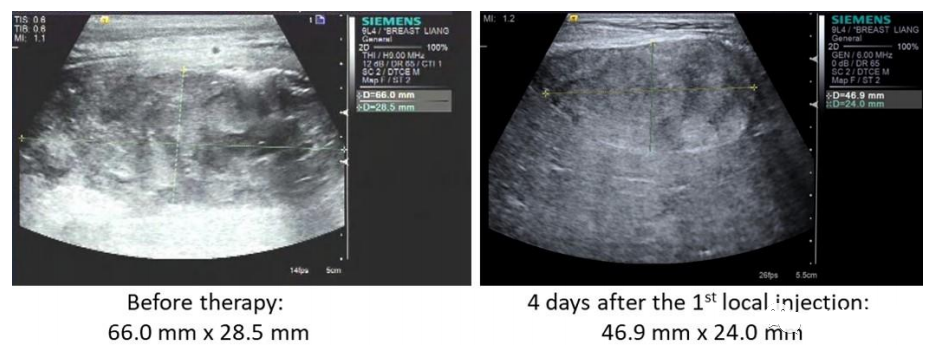

本研究中,采用局部输注 NKG2Dp CAR-NK的方式治疗了3 例转移性结直肠癌患者。前两例患者腹腔输注低剂量 CAR-NK 细胞后,可观察看腹水生成量减慢以及腹水样本中肿瘤细胞的数量急剧减少。第三例肝转移瘤患者采用超声引导下瘤内经皮注射和腹腔内灌注方式输注 CAR-NK细胞后,多普勒超声可见肝部肿瘤快速缩小,正电子发射断层扫描(PET-CT)提示经治疗的肝病灶为完全代谢反应。3 例患者在治疗过程中均无出现3级或以上的不良事件。

第3例患者多普勒超声成像显示局部注射 CAR-NK 细胞降低肝转移病灶肿瘤负荷